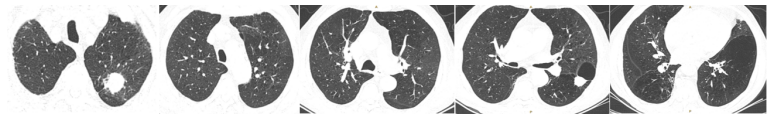

2023年5月24日多排CT胸部平扫CT所见:左肺上叶多发空洞,较前明显进展;右肺下叶支气管壁增厚伴条索影,两肺支气管旁多发絮状影及结节影,局部较前稍明显;左侧少许胸腔积液,伴左肺膨胀不全(图3)

图片

图3 患者胸部CT